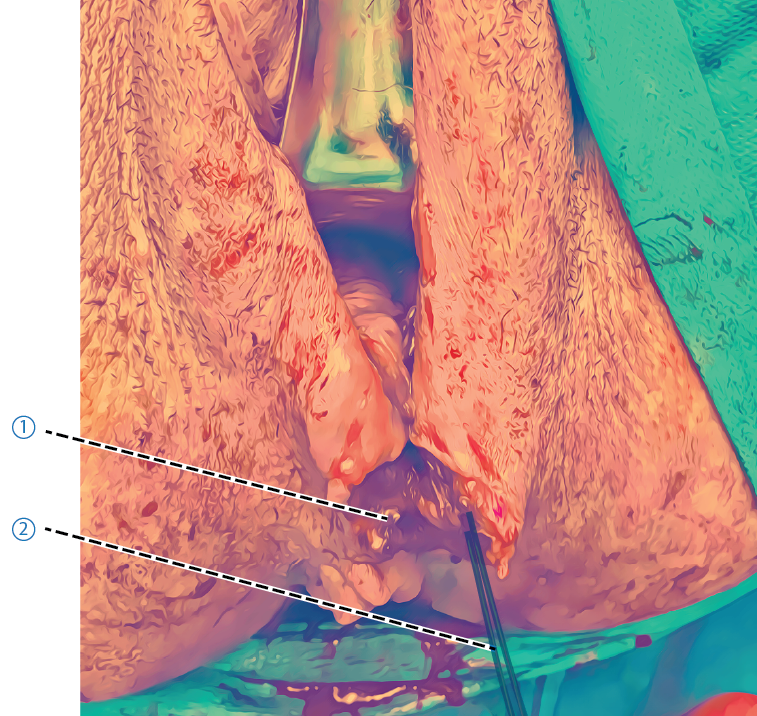

Adaptera muskelfästet mot medellinjen med en multifilament 2/0 tråd (t ex Vicryl® eller Polysorb® 2/0). När de inre delarna (rektovaginala fascian, m puboperinealis och m transversus perinei profundus) är väl suturerade har den inre delen av perinealkroppen återställts och vaginalslemhinnans sårkanter möts. Vaginalslemhinnan behöver inte alltid sutureras, men sys vid behov fram till hymen med samma tråd eller med en multifilament tråd med snabb resorptionstid, t ex Vicryl rapide® 2/0. När muskelfästena är adapterade är hymenkransen symmetrisk och kan lämnas osuturerad.- Hymen

- Oknuten sutur

- Inre delar av perinealkroppen